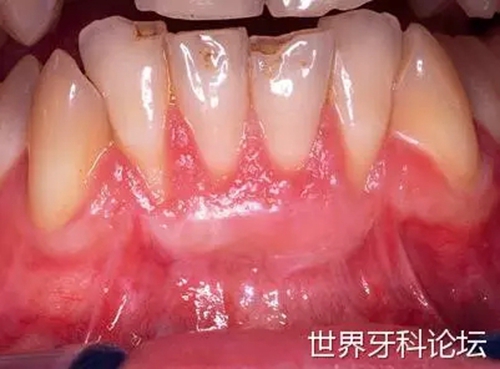

病例3

一位65歲女性患者,前牙區(qū)種植體折斷,#12到#22缺失(圖13)。植入種植體時(shí),唇側(cè)骨板厚度不足,美學(xué)表現(xiàn)不佳。故使用骨替代材料(無(wú)機(jī)小牛來(lái)源羥基磷灰石)及可吸收膠原膜進(jìn)行再生性手術(shù)(圖14-17)。

圖13:#12到#22缺失,種植體折斷。

圖14-17:植骨進(jìn)行再生性手術(shù)。

仔細(xì)縫合避免創(chuàng)口開(kāi)裂,防止愈合期并發(fā)癥發(fā)生。進(jìn)行生物調(diào)節(jié)加速骨愈合促進(jìn)移植物的融合。使用平頭手機(jī)以MSP模式、10Hz、0.5W(LightWalkerATS, Fotona, Ljubljana, Slovenia)、60s秒每位點(diǎn),每隔一天進(jìn)行生物調(diào)節(jié),持續(xù)10天(圖18)。

圖18:縫合后進(jìn)行生物調(diào)節(jié)。

三個(gè)月后,組織健康,厚度足夠,二期手術(shù)同時(shí)進(jìn)行臨床冠修復(fù)(圖19,20)。種植體植入6個(gè)月后,組織穩(wěn)定,可以進(jìn)行正式修復(fù)(圖21)。